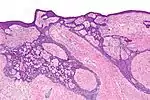

| Type | Histopathology | Other characteristics | Image |

| Morpheaform basal-cell carcinoma (also known as "cicatricial basal-cell carcinoma", and "morphoeic basal-cell carcinoma") | Narrow strands and nests of basaloid cells, surrounded by dense sclerotic stroma.[29] | Aggressive[26]: 748 [27]: 647 | ![]() |

| Infiltrative basal-cell carcinoma | Deep infiltration.[27]: 647 | Aggressive[27]: 647 | |